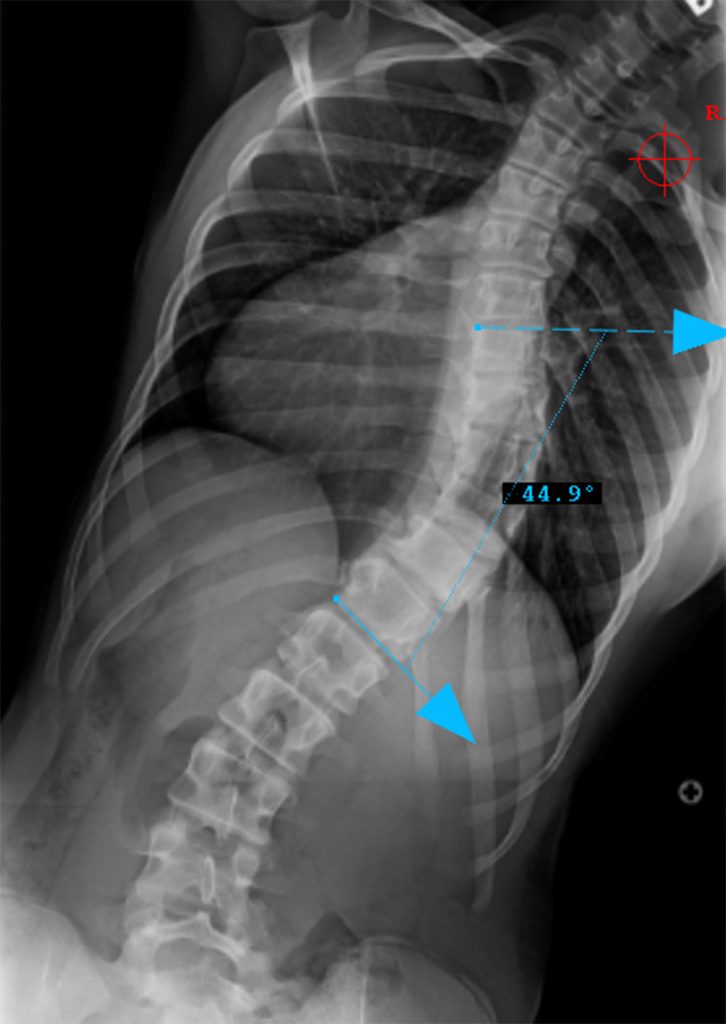

Thoracic curve major, other curves non-structural (bend out to <25o)

CSVL between pedicles at apex (L5)

T5-T12 in the 10-40o range

Therefore, Classification is Type 1AN